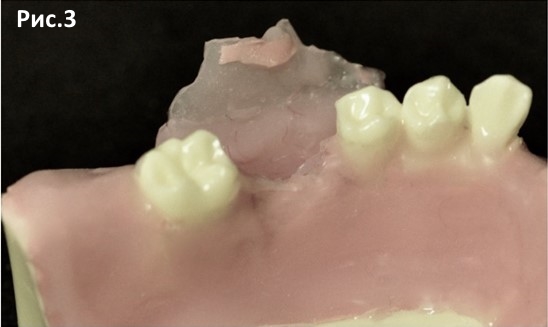

По краю альвеолярного гребня в области кератинизированной десны проводим разрез до кости под углом 45 градусов к поверхности мягких тканей. Отслаиваем полноценный слизисто-надкостничный лоскут с язычной стороны на несколько миллиметров. С вестибулярной стороны полноценный слизисто- надкостничный лоскут отслаиваем до конца прикрепленной слизистой (СДС слизисто-десневого соединения). Далее на границе проводим горизонтальный разрез надкостницы. После этого проводим вертикальные послабляющие мезиальные и дистальные разрезы слизистой изнутри наружу, без рассечения надкостницы. Тупым распатором отделяем слизистую от надкостницы. Это позволит нам в дальнейшем мобилизовать лоскут без натяжения. Рис.2 Рис.3